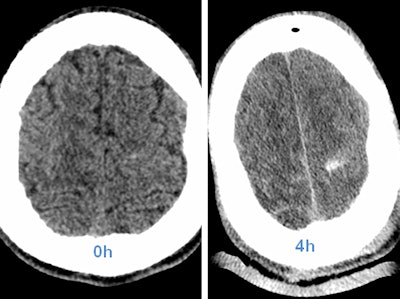

The main cause of missed injuries, such as pancreatic and diaphragmatic lesions, bladder rupture, and pseudoaneurysms, is the presence of multiple more evident injuries, such as solid organ lesions, that become the focus of attention.

"Bowel injuries, for example, are often missed in CT examinations because in polytrauma patients some specific bowel findings can be misdiagnosed, such as the presence of free small air collections misinterpreted as normal intraluminal air," Basilico noted.

Radiologists can overcome misdiagnosis by routinely using lung or bone window settings that help differentiate fat from air or multiplanar reconstructions, useful in vascular injuries and skeletal lesions. Moreover, a specific CT protocol for trauma patients, including unenhanced and multiphasic contrast-enhanced CT and, when necessary, a CT cystogram, will help radiologists detect an intra- and extraperitoneal bladder rupture in a case of multiple pelvic fractures, for example.